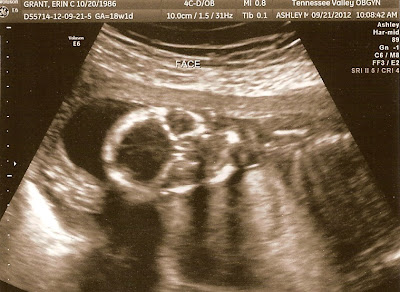

Also, here are our ultrasound pictures from last week…

![]() |

| Her skull…she’s working on her Halloween costume early! :) |